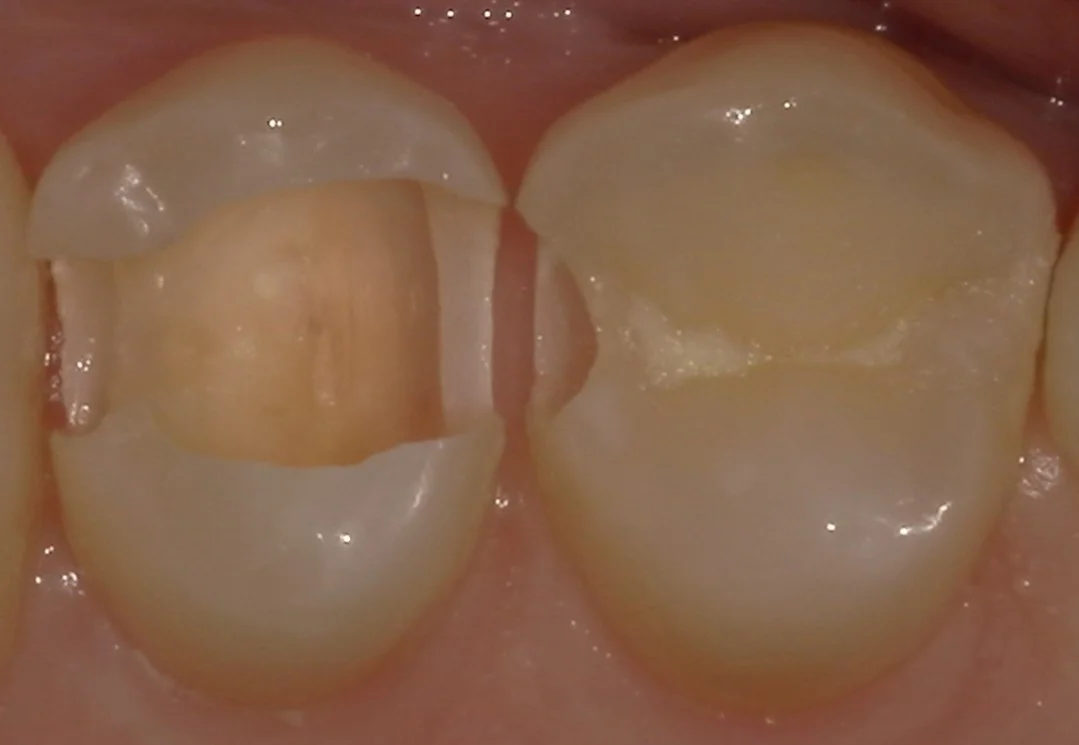

そして虫歯を見えやすくしたのがこちらです。

内面が黒い部分と白い部分に分かれていますが、これは虫歯の種類が違うためです。

黒い部分が慢性う蝕といって、非常にゆっくりと横に広がるような形で進む虫歯です。

大して白い部分は急性う蝕といって、急速に狭く深く進行していく虫歯になります。

そして急性う蝕の場合は基本的に白く透けて見えないため、発見が遅れがちになってしまうのが怖い所ですね。

そういう点でも定期的なレントゲン診査というのは必須になってくると思います。